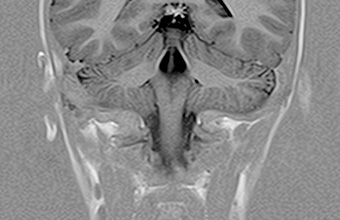

MR djece

MR djece u ‘VURI’ nudi izuzetno kontrastne snimke zahvaljujući djeci prilagođenim protokolima obrade koji koriste sigurne tehnike ultra-brzog snimanja i kompenzacije pokreta tijela.